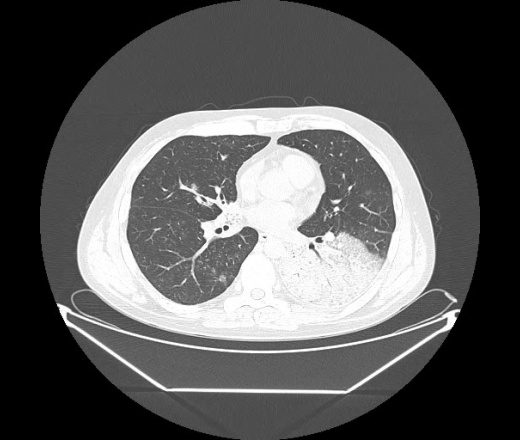

М. 1984 г.р.  Лихорадка 39, кашель , одышка.. и надоевший всем вопрос- "типично ли для ковид?" ( в настоящее время на него обязательно нужно дать ответ в своем протоколе)

На мой взгляд нетипично для ковид: много центрально-расположенных поражений, лобарное поражение нижней доли слева. 50/50

Не типичая картина для ковид.

КТ-признаки двусторонней бактериальной пневмонии.

Все верно, здесь абсолютно нетипичная картина, несмотря на матовое стекло с ретикулярными изменениями, но почему-то  посчитали иначе. Кстати,  "малыша" не заметили)?

Добавил 6 день